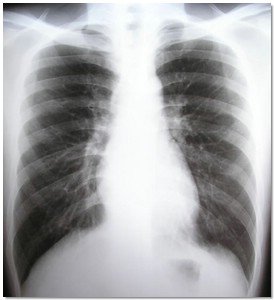

Los investigadores del proyecto se han centrado en dos aspectos básicos del diagnóstico y seguimiento de los pacientes con EPOC. Por un lado, han evaluado la eficacia en el uso de la espirometría, prueba que se realiza de forma rutinaria en los servicios de neumología, en los Centros de Atención Primaria, ya que juegan un papel esencial en el seguimiento de enfermedades respiratorias crónicas como el EPOC o el asma. Para ello se ha diseñado una aplicación que permite desplegar un programa de control de calidad de las mismas. Transcurridos 12 meses de aplicación del programa, los resultados obtenidos demuestran un aumento en la calidad de las mismas, permitiendo un mejor diagnóstico o seguimiento de la EPOC.

El otro objetivo del proyecto ha sido realizar un programa de rehabilitación para pacientes diagnosticados con EPOC. El programa se divide en dos periodos. En el primero el paciente asiste a un entrenamiento en el hospital durante dos meses; y en el segundo se le propone una rutina de ejercicio fuera del hospital para que practique actividades físicas comunes –caminar, ir en bicicleta, etc.-. El control del paciente se realiza desde su domicilio mediante un pulsioxímetro conectado a un teléfono móvil que envía los datos al centra de salud.

El estudio ha demostrado que el hecho de alcanzar niveles adecuados de actividad física diaria, junto con el programa de rehabilitación controlado, es eficaz para mantener e incluso incrementar los efectos del entrenamiento en pacientes con EPOC. Los parámetros medidos en cuanto a calidad de vida y capacidad de esfuerzo mejoran considerablemente en los pacientes que han seguido el programa, como demuestra la medida de la tolerancia al ejercicio, que aumenta de forma notable en el grupo intervenido respecto al control. Con esta tecnología móvil se consigue educar a personas con esta enfermedad, promover un estilo de vida saludable y mejorar el tratamiento –farmacológico y no-farmacológico -, lo hace que los pacientes incrementen su calidad de vida e ingresen con menos frecuencia en el hospital.

Las conclusiones a las que se han llegado con este proyecto indican que el hecho de realizar un diagnóstico precoz y el pautar una rutina de ejercicio controlada y seguida por los especialistas, son componentes clave en el manejo de estos pacientes, aumentando su esperanza de vida y contribuyendo a la contención del gasto sanitario.